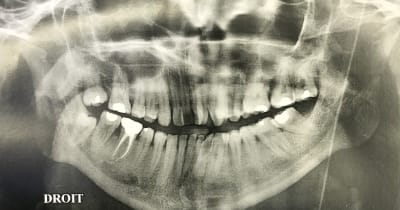

En attendant que le nouveau réponde ... Dans un style différent : 38 ans . très complexé. Aucun dentiste n’a voulu le toucher (pour le secteur antérieur) . Je lui ai dit qu’il fallait lui déglinguer la mâchoire. Sauf qu’il ne veut pas faire de chirurgie orthognatique, c’est sa seule condition . Par contre est prêt à mettre n’importe quel prix pour retrouver un beau sourire. N’est ni fermé à l’ortho , ni fermé à l’implantologie.

Photo de la pano qu’il m’a ramenée.

On se passera des : faut faire un détartrage :) , ou faut qu’il se lave les dents.

Ça c’est un cas qui s’apparente au cas du nouveau . Le problème dans ce genre de cas traité uniquement prophétiquement c’est qu’on n’obtient pas forcément une meilleure occlusion :) .

Dans le cas du nouveau il faut vraiment faire une intervention osseuse ++++, encore plus que sur celle-ci

Le cas du début c'est avant tout une supraclusie carabinée.